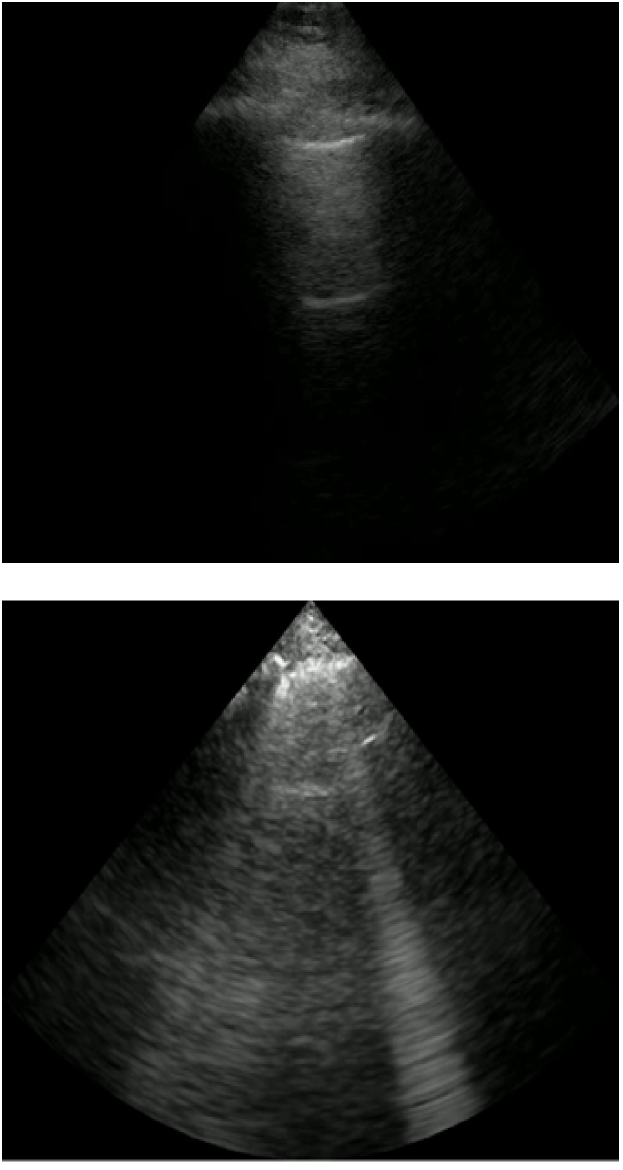

The LUS interpretative workflow addressed in this work has been described as a decision tree [19]. After determining the view, the interpreter traverses down the tree to look for increasingly specific artefacts that reduce a possible differential diagnosis. We focus on three binary classification tasks for LUS image interpretation: view classification (View), A-line versus B-line classification (A/B), and pleural effusion detection (PE). The former is applicable to parenchymal LUS views, and the latter to pleural LUS views. Table 1 summarizes these tasks, and Figure 1 displays emblematic examples for each class.

Refer to caption

(a) View: Parenchymal (top), pleural (bottom)

(b) AB: A-lines (top), B-lines (bottom)

(c) PE: No PE (top), PE (bottom)

Figure 2: Examples of each class for each LUS binary classification task: View (a), AB (b), and PE (c).